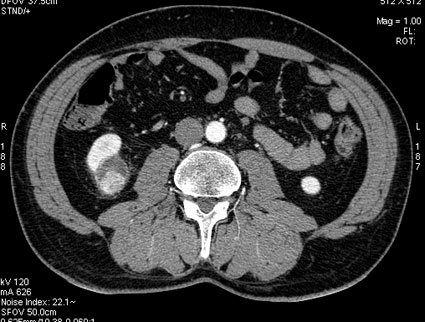

КТ- реконструкция

se026.jpg (19.71 КБ) 1002 просмотра